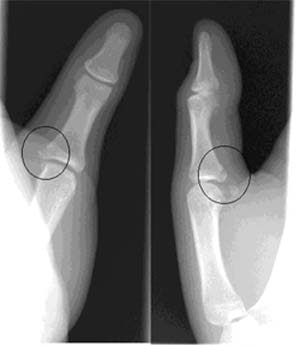

| Coned anteroposterior (left image) and oblique (right image) views optimally demonstrate the oblique and slightly comminuted fracture (center of circles). Mild soft tissue swelling is also visible adjacent to the fracture site. Images courtesy of Dr. Douglas P. Beall. |